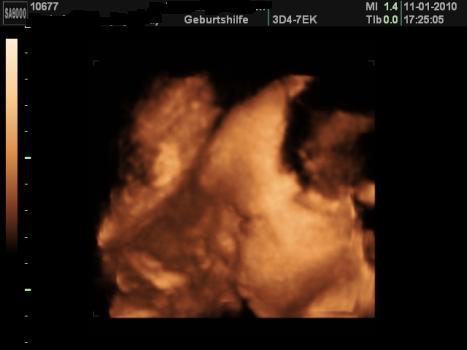

Bild zu